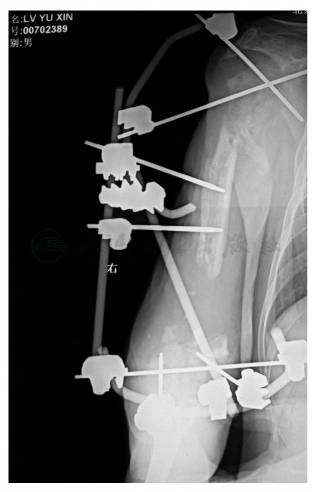

伤后7个月就诊时右上臂外固定架固定,右上臂近、中段外侧有一长21cm、宽9cm的瘢痕,且与肱骨贴附。肩部前外侧有1个直径2cm的窦道(图8),肱骨近端外固定架的2枚斯氏针已经松动。右肘关节固定于屈肘80°位,肘后有1个黄豆大小的窦道(图9)。右前臂内侧感觉迟钝,右手伸指、伸拇、伸腕不能,拇指外展不能。松开外固定架连杆后,肱骨近、远端有异常活动。X线片显示右肱骨近端粉碎骨折,骨折累及干骺端,肱骨近端骨质有被吸收的表现,外固定架的2枚斯氏针交叉将肱骨头固定于肩胛盂;肱骨中段骨端游离,与肱骨髁有约6cm长的骨缺损(图10)。肱骨髁间骨折,外固定架远端的2枚半针分别拧在肱骨内、外髁。右桡骨骨折复位好,可见髓内针固定,骨折线消失(图11)。

图8 术后7个月,右肱骨以外固定架固定。右上臂近、中段外侧有一长21cm、宽9cm的瘢痕,其上散在创面覆盖。右肩部外固定架可见2个针道均有炎性反应,肩部前外侧有一个直径约为2cm的窦道,有脓性分泌物渗出

图10 术后7个月,X线片肱骨近端粉碎骨折,骨折累及干骺端,肱骨近端骨质有被吸收的表现,干骺端骨质不完整。外固定架的2枚斯氏针交叉将肱骨头固定于肩胛盂。与肱骨髁之间有约6cm长的骨缺损